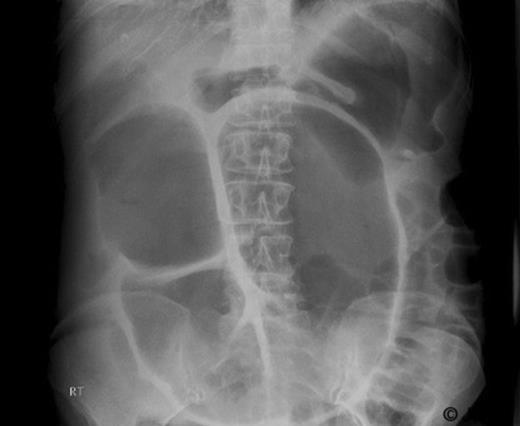

In a majority of cases, the diagnosis is confirmed at exploratory laparotomy. In this case, a CT scan done five months before the acute presentation revealed colonic dilatation and local relapse at the splenic flexure along with liver metastasis and peritoneal disease (Figure 2). A diagnosis of colonic mucocele was not made and the air fluid level in the closed loop was thought to be due to competent ileocaecal valve. On hindsight, the absence of intestinal obstruction in spite of impressive colonic dilatation in the CT scan should have raised the suspicion of an evolving colonic mucocele. This reinforces the need for a high index of suspicion so that the diagnosis can be made pre-operatively and the patient managed conservatively.

CT abdomen showing dilatation of ascending and transverse colon upto splenic flexure with air fluid levels.